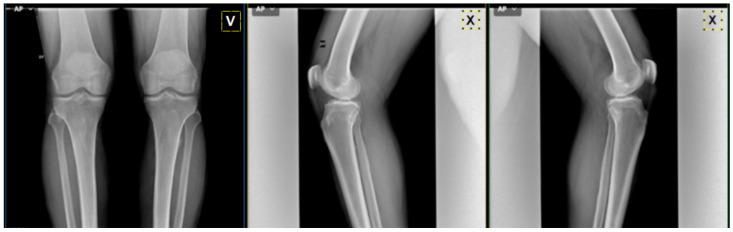

In computer-aided medical diagnosis, deep learning techniques have shown that it is possible to offer performance similar to that of experienced medical specialists in the diagnosis of knee osteoarthritis. In this study, a new deep learning (DL) software, called "MedKnee" is developed to assist physicians in the diagnosis process of knee osteoarthritis according to the Kellgren and Lawrence (KL) score. To accomplish this task, 5000 knee X-ray images obtained from the Osteoarthritis Initiative public dataset (OAI) were divided into train, valid, and test datasets in a ratio of 7:1:2 with a balanced distribution across each KL grade. The pre-trained Xception model is used for transfer learning and then deployed in a Graphical User Interface (GUI) developed with Tkinter and Python. The suggested software was validated on an external public database, Medical Expert, and compared with a rheumatologist's diagnosis on a local database, with the involvement of a radiologist for arbitration. The MedKnee achieved an accuracy of 95.36% when tested on Medical Expert-I and 94.94% on Medical Expert-II. In the local dataset, the developed tool and the rheumatologist agreed on 23 images out of 30 images (74%). The MedKnee's satisfactory performance makes it an effective assistant for doctors in the assessment of knee osteoarthritis.

在计算机辅助医学诊断中,深度学习技术已表明,在膝关节骨关节炎的诊断中能够提供与经验丰富的医学专家相媲美的诊断性能。在本研究中,开发了一种名为“MedKnee”的新型深度学习(DL)软件,以根据凯尔格伦和劳伦斯(KL)评分协助医生进行膝关节骨关节炎的诊断过程。为完成此任务,从骨关节炎倡议公共数据集(OAI)获取的5000张膝关节X光图像按照7:1:2的比例分为训练集、验证集和测试集,且在每个KL等级上分布均衡。预训练的Xception模型用于迁移学习,然后部署在使用Tkinter和Python开发的图形用户界面(GUI)中。所建议的软件在外部公共数据库“医学专家”上进行了验证,并在本地数据库中与风湿病专家的诊断进行了比较,由放射科医生参与仲裁。MedKnee在医学专家-I上测试时准确率达到95.36%,在医学专家-II上为94.94%。在本地数据集中,开发的工具与风湿病专家在30张图像中的23张上达成一致(74%)。MedKnee令人满意的性能使其成为医生评估膝关节骨关节炎的有效助手。